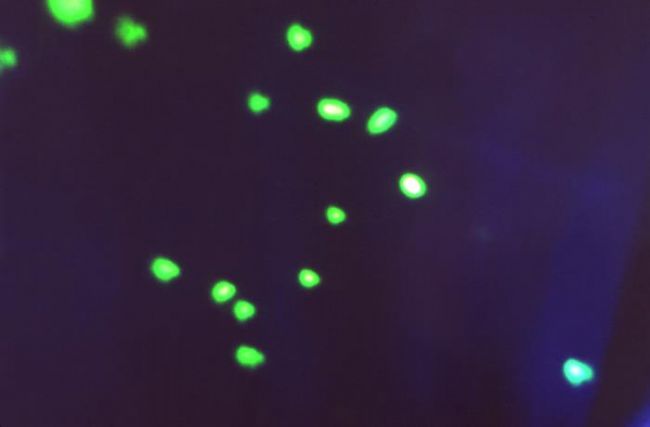

在顯微鏡下的形態是球形或卵圓形,直徑0.6~1.0um,多數呈鏈狀排列,經革蘭氏染色后,顯微鏡下呈紫色。

如果想高效觀察鏈球菌,還可以使用熒光顯微鏡,經熒光染色后,可見高特異性熒光反應,鏈球菌呈綠色熒光